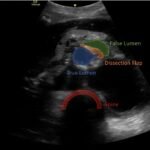

Although uncommon, acute aortic dissections are a life-threatening, cannot miss diagnosis for the emergency medicine clinician. Point of care ultrasound can play an integral role in the initial work up of the undifferentiated patient. While not initially utilized to make the diagnosis of aortic dissection, the ultrasound images obtained in this case describe key findings on ultrasound vital for an emergency clinician to recognize. It is essential for emergency medicine clinicians to differentiate an aortic dissection from other causes of chest pain and abdominal pain because the quick mobilization of resources plays a key role in the management and outcome of such patients.

Aortic dissection, vascular, dissection flap, back pain, point of care ultrasound, POCUS.